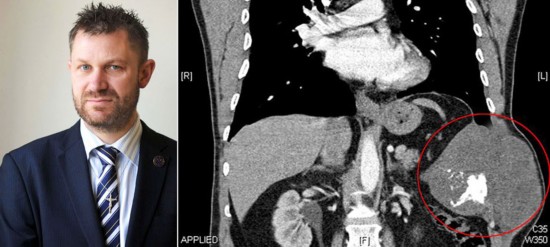

【英男子体内切除三斤重肿瘤 医生用水泥补胸】

用水泥补胸!这听上去真匪夷所思,但在英国这样的事确实发生了,2012年5月,一名男子之前体内有一个跟西瓜差不多大的肿瘤,而这个肿瘤的位置在他的肋骨内侧。在将他的肿瘤切除之后,医师们使用了25平方厘米的丙烯酸水泥来代替他的肋骨,然后从他肩膀处提取了肌肉来修补隔横膜。